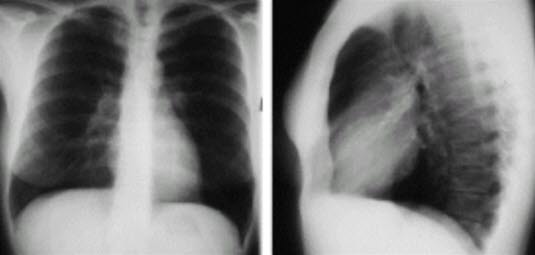

- RTG klatki piersiowej

- RTG klatki piersiowej przede wszystkim jako element diagnostyki różnicowej.

- Przy dużych zatorach płucnych ewentualnie poszerzenie tętnic płucnych, ograniczona perfuzja zajętych segmentów, ogniska niedodmy.